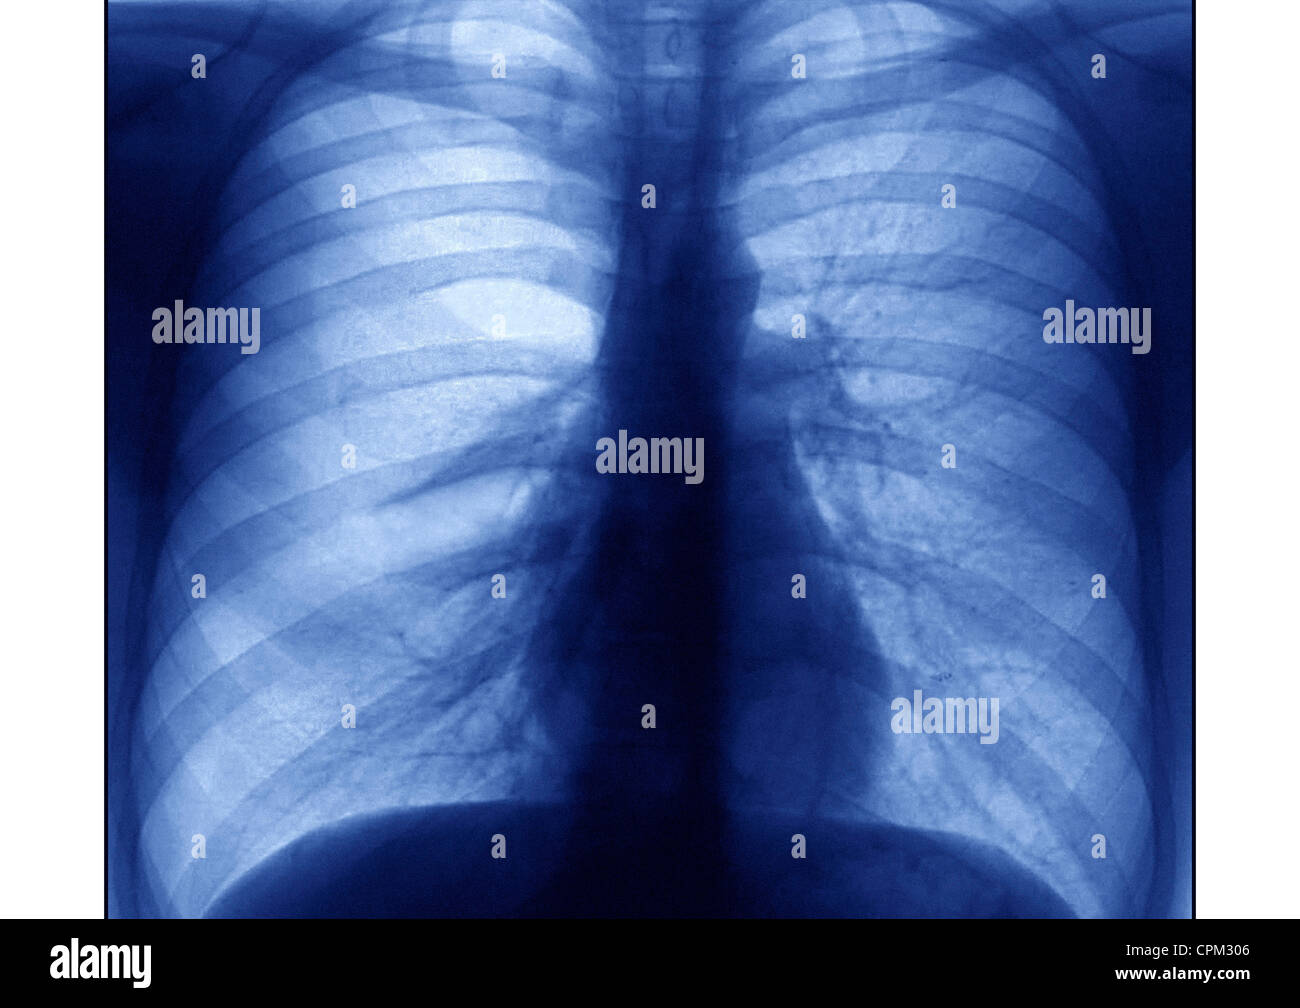

ASTHMA, XRAY Stock Photo Alamy Does Asthma Show On An X Ray plain chest radiographs can be normal in up to 75% of patients with asthma. Reported features of asthma include: Acute airway narrowing due to bronchial smooth muscle contraction. But they may use them to help rule out other conditions and. Does Asthma Show On An X Ray.